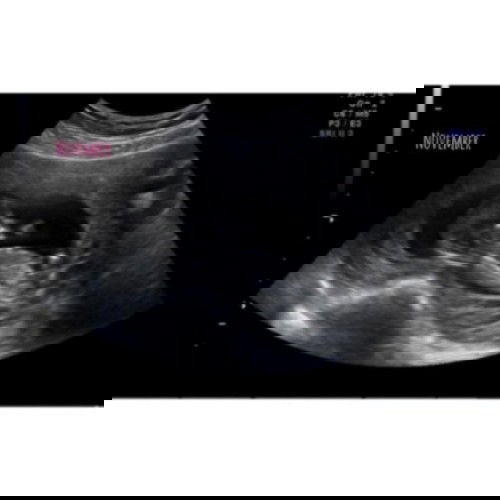

12minggu ??❤

Baby November